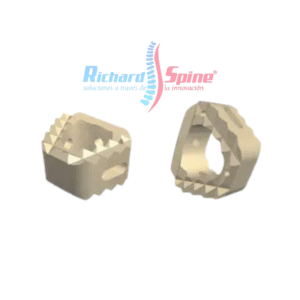

Malla de Titanio para Columna Cervical

- La malla de titanio está disponible en diferentes alturas para cada patología y condiciones anatómicas. arquitectura abierta para malla de titanio permite la fusión ósea y optimiza el crecimiento óseo y sus anillos extremos paralelos para restaurar la alineación espinal normal y resistir el hundimiento. mientras tanto, se utiliza malla de titanio para Trauma, tumor, espondilolistesis, disco degenerativo enfermedad.